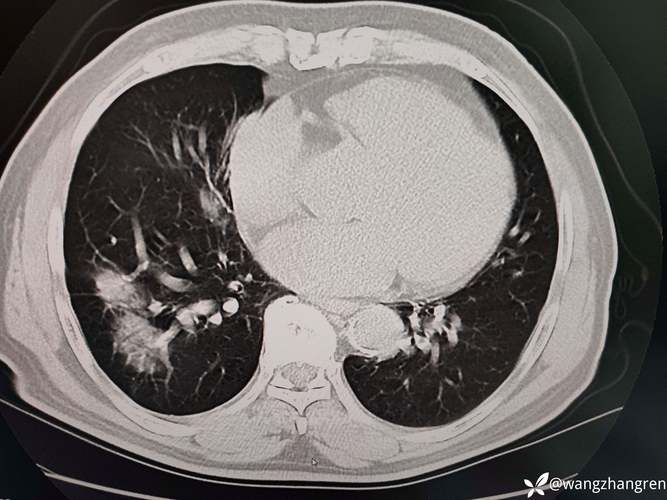

| 病例分析 | 综合病例影像(如肝脏占位、骨肿瘤),要求诊断依据及鉴别诊断 | 结合影像特征(如强化方式、信号特点)、实验室检查及临床资料,逻辑严谨 |